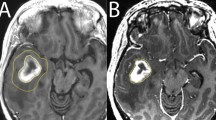

Six patients with histologically verified gliomas of the conus medullaris (two astrocytomas, two ependymomas, two myxopapillary ependymomas) were diagnosed and studied. There were four men and two women ranging in age from 23 to 47 years. Predominant initial symptoms were back pain (four cases) and leg weakness (two cases). The most common findings on admission were flaccid paparesis with impaired sensation and bladder dysfunction. Postoperative MR images with more than 95% removal of a tumour were defined as ‘subtotal removal’ (noted in two of six cases), and less than 95% as ‘partial removal’ (four of six cases). All patients had postoperative radiotherapy, and the two patients with an astrocytoma underwent chemotherapy. During the follow up period ranging from 2 to 7 years, there was no tumour recurrence or regrowth on MR images except in a patient with a malignant astrocytoma, who indeed died from intracranial dissemination 2 years after surgery. Adjuvant therapy following the excision of a spinal glioma is also discussed.